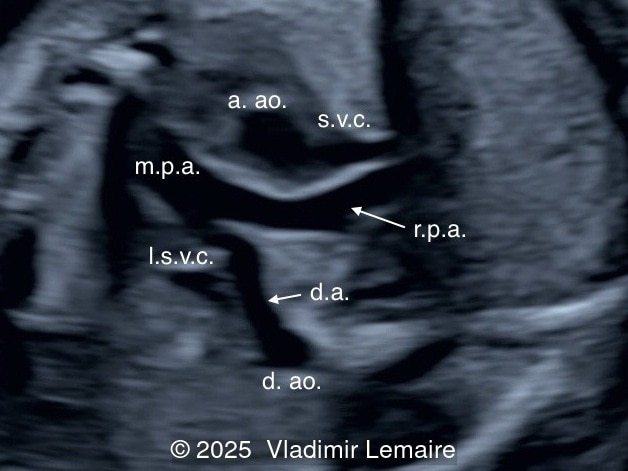

Three-vessel-trachea view with color Doppler.

Image 5 Three-vessel-trachea view with color Doppler.

In the images below, the abbreviations are as follows: RA: right atrium; RV: right ventricle; LV: left ventricle; MV: mitral valve; LA: left atrium; FO: foramen ovale; SVC: superior vena cava; LSVC: left superior vena cava; PV: pulmonary veins; PA: pulmonary artery; MPA: main pulmonary artery; RPA: right pulmonary artery; AO: aorta; dAO: descending aorta; aAO: ascending aorta; DA: ductus arteriosus; T: trachea; * marks the ventricular septal defect.

Image 6 Three-vessel-trachea view with color Doppler.